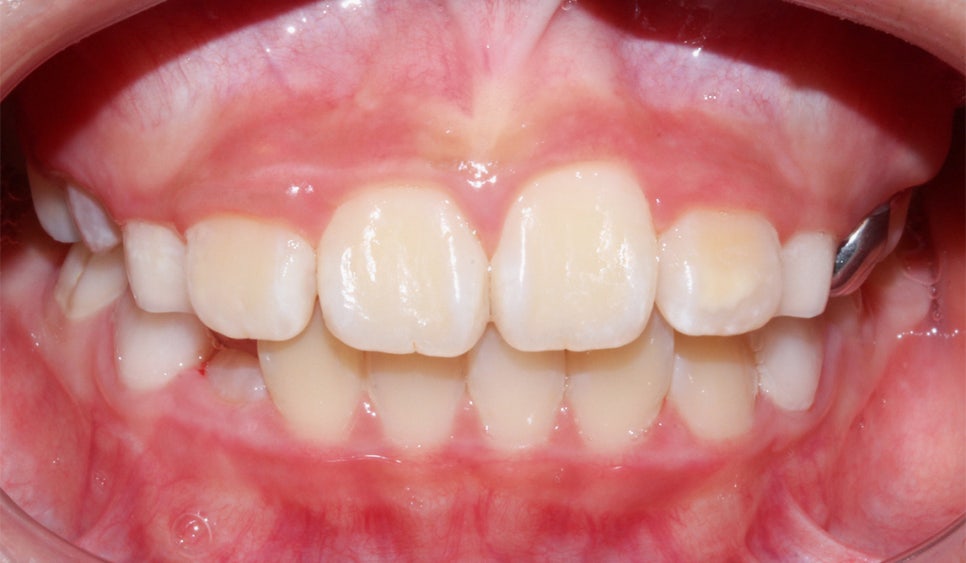

환자분의 상태를 살펴보면

치아가 날 공간이 부족하거나 치아가 나오는 방향에서

앞니가 앞으로 나오고 다른 치아가 기울어지면서

거꾸로 물리는 현상이 발생한 걸로 보여요.

안 모의 변화 모습이에요.

상/하악 전치 모두 상당량이 후방으로 이동이 되었기

때문에 훨씬 심미적으로 변화가 되었어요.

<24개월 교정 완료 모습>

전체적으로 치아가 크게 개선이 되었어요.